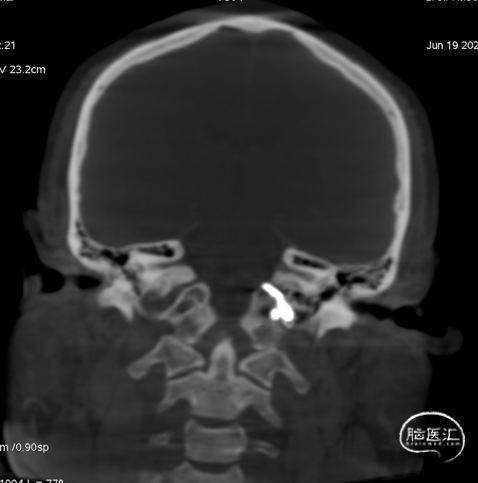

术前CT见左侧眼上静脉扩张

术后铸胶形态及CT下铸胶位置,可见瘘口位于左侧舌下神经管区域。